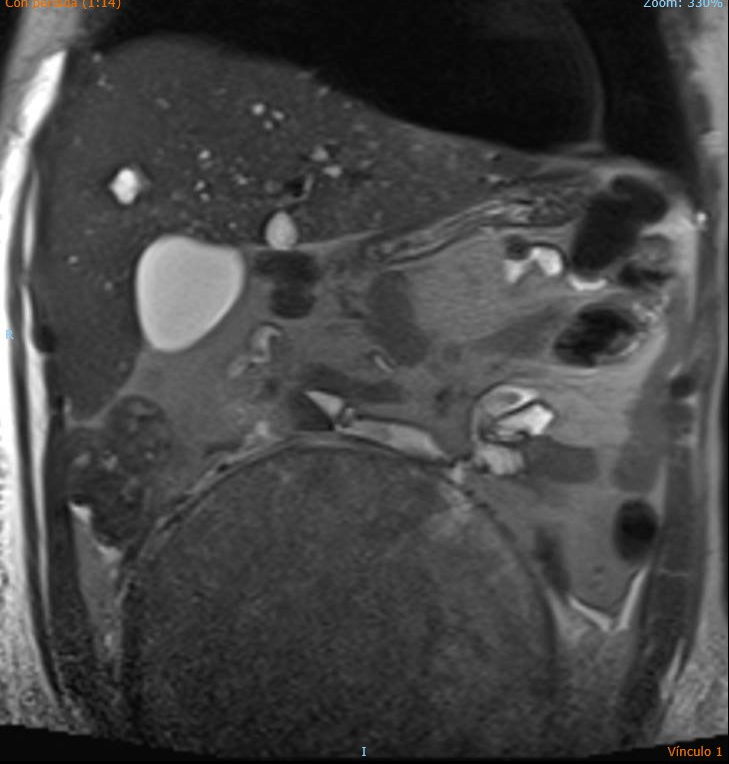

Ecografía de abdomen de Urgencias: se observa gran LOE pélvico abdominal ecogenicidad heterogénea, con hígado aumentado de tamaño y con imágenes hipoecoicas. Uterohidronefrosis derecha.

Igualmente se concluyó el estudio con ecografía de testículo y RNM.

En Atención Primaria, los meses previos fue tratado como una lumbalgia de cáracter crónico. La disnea por la que se derivó fue fruto de un TEP. El diagnóstico definitivo: Seminoma con hígado metastásico con adenopatías derechas y compresión de ilíaca derecha.